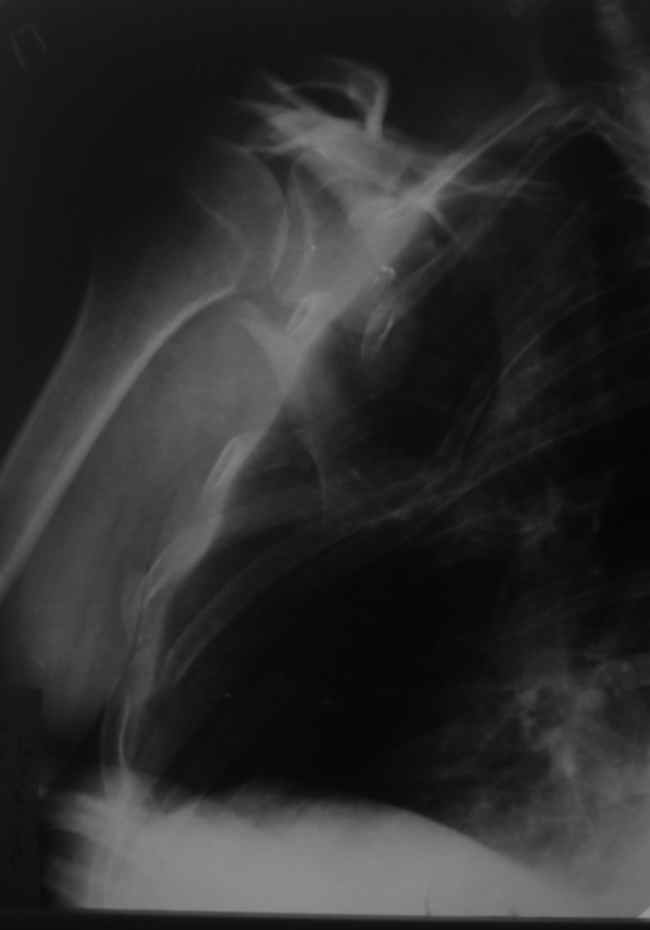

Уважаемые коллеги, помогите определиться с тактикой. Больной 1953гр, травма на стройке, придавило тяжелымпредметом. Сейчас в сознании, стабилен, плевральная полость задренирована. Предполагаем синтез ключицы, если бы не переломы ребер, установили бы шину ЦИТО.Есть у кого опыт открытого/закрытого синтеза подобной лопатки? Что делать с клювовидным отростком? Спасибо, Моисеев Ю.И.

К сожелению доктор который занимается грудной клеткой в отпуске, у себя нашёл только вот этот снимок

С Уважением А.Миронов